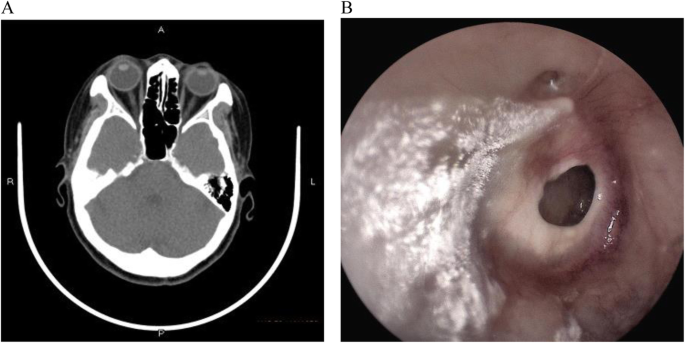

(*) Ghi chú:

(A) Viêm tai giữa mạn tính không hoạt động bên trái.

(B) Viêm tai giữa mạn tính hoạt động bên phải, với màng nhĩ bị viêm và niêm mạc tai giữa ẩm ướt. Hình ảnh nội soi tai sau phẫu thuật vá màng nhĩ (tympanoplasty) sau 3 tháng theo dõi

(C) Viêm tai giữa mạn tính không hoạt động dạng niêm mạc

(D) viêm tai giữa mạn tính hoạt động dạng niêm mạc